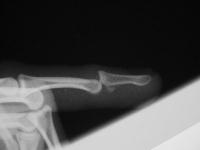

The injury:dorsal DIP fracture dislocation of the ring finger of a 16 year old male sports hopeful.

Unstable even in a well molded splint.